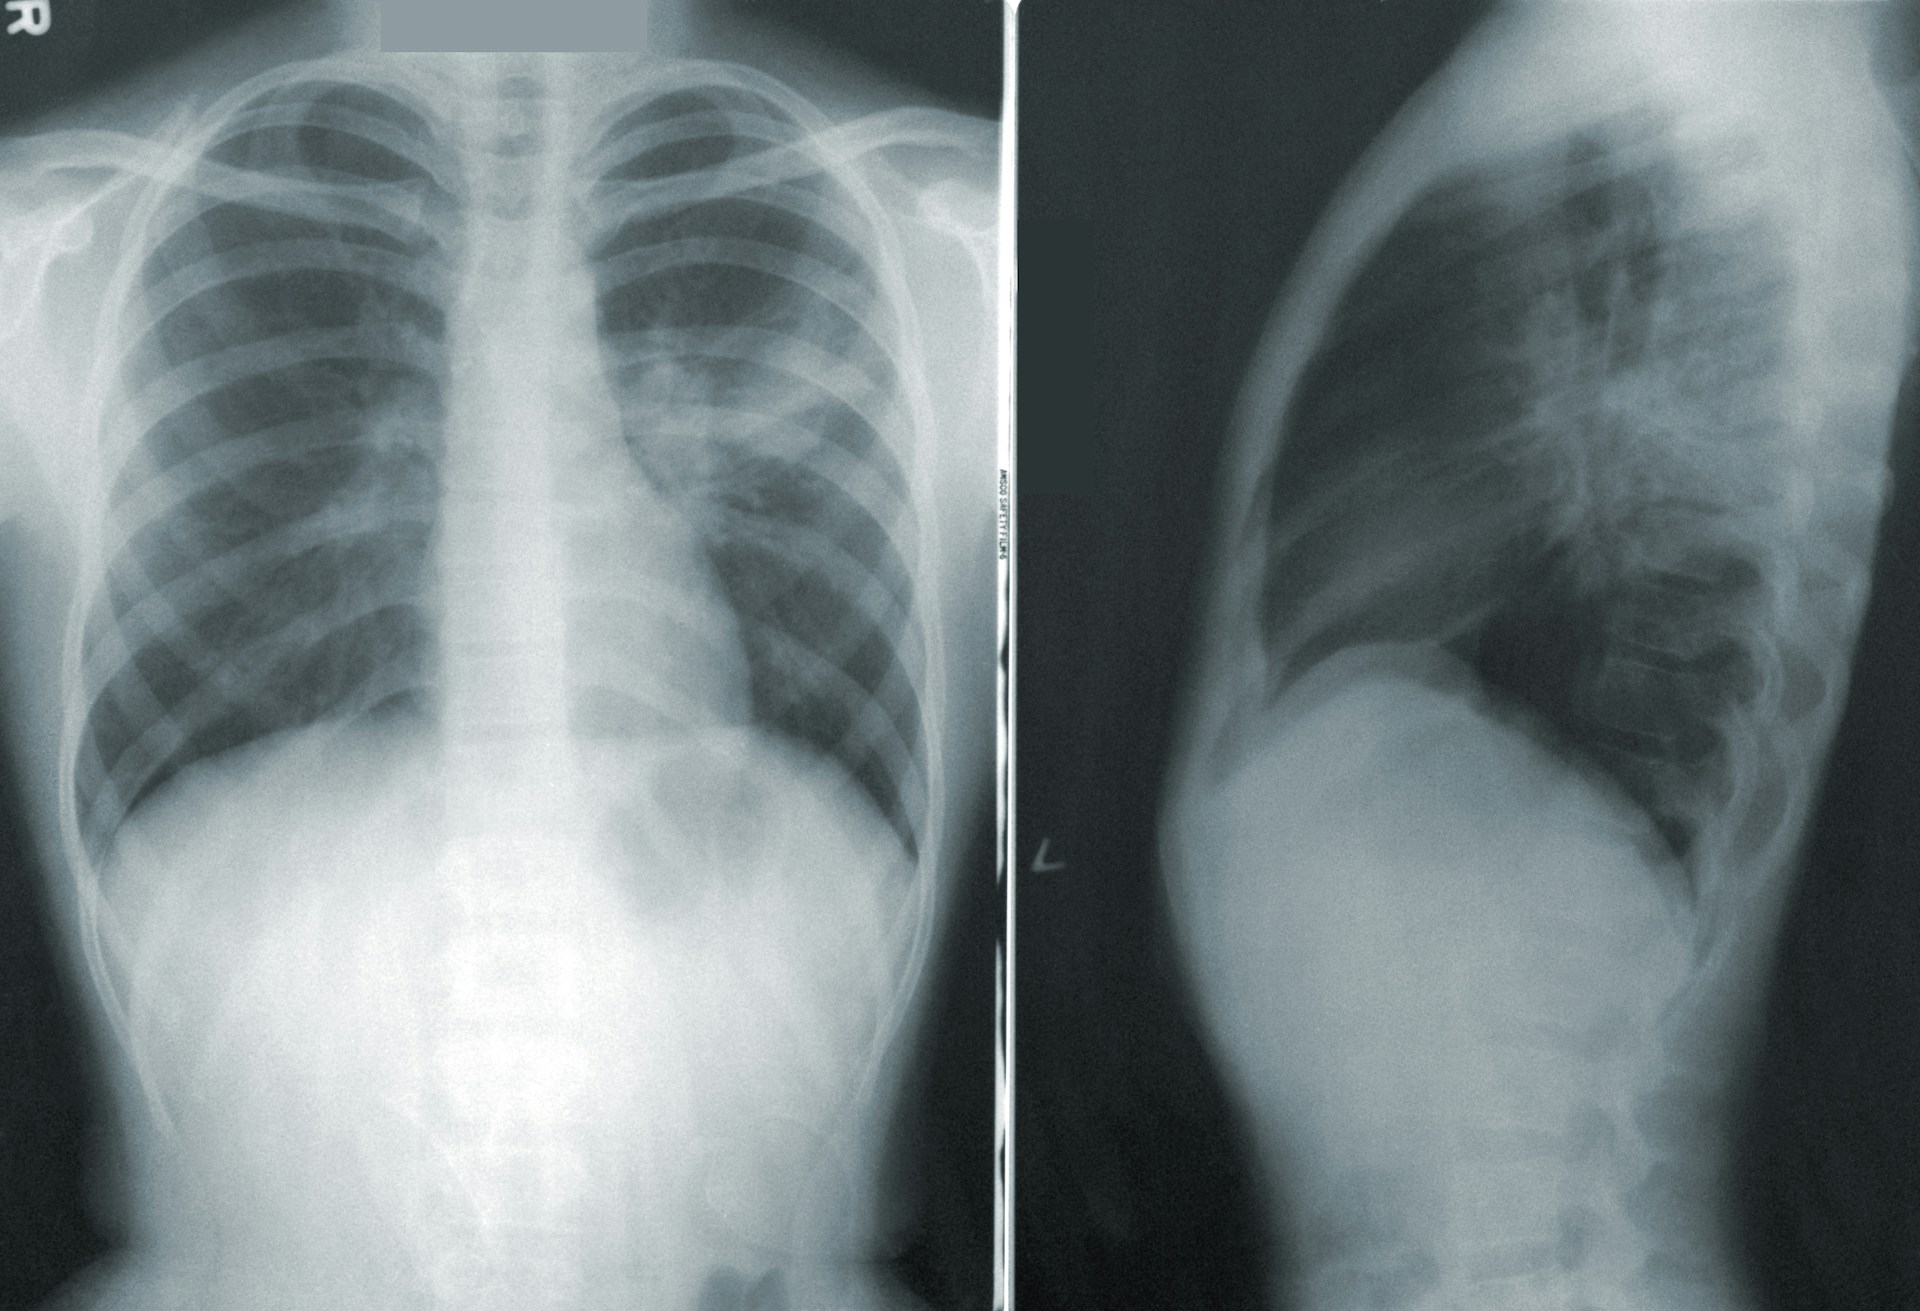

Врачи настоятельно рекомендуют следить за симптомами и при необходимости обращаться за медицинской помощью. Среди основных симптомов микоплазменной пневмонии можно выделить:

• Кашель;

• Лихорадка;

• Одышка;

• Боль в груди.

Важно отметить, что микоплазменная пневмония чаще всего возникает как осложнение после вирусных инфекций, таких как грипп или COVID-19. Поэтому вакцинация против этих заболеваний может служить профилактикой.